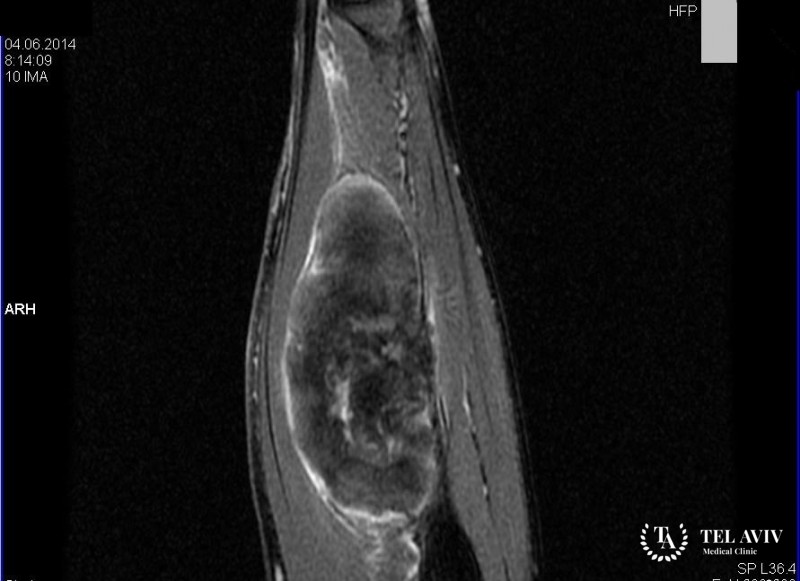

После визуального осмотра, пальпации и сбора анамнеза, может понадобиться пройти обследование с помощью лабораторных методов, и современных, информационных аппаратов, таких как УЗИ, МРТ, КТ, ПЭТ. Израильская клиника Tel Aviv Medical Clinic располагает самым новейшим оборудованием, чтобы со 100% точностью установить характер опухоли, форму, структуру, очаг поражения, стадию роста. Опытные врачи отделения нейрохирургии проведут операцию по удалению опухоли, применят по необходимости лучевую терапию или химиотерапию.